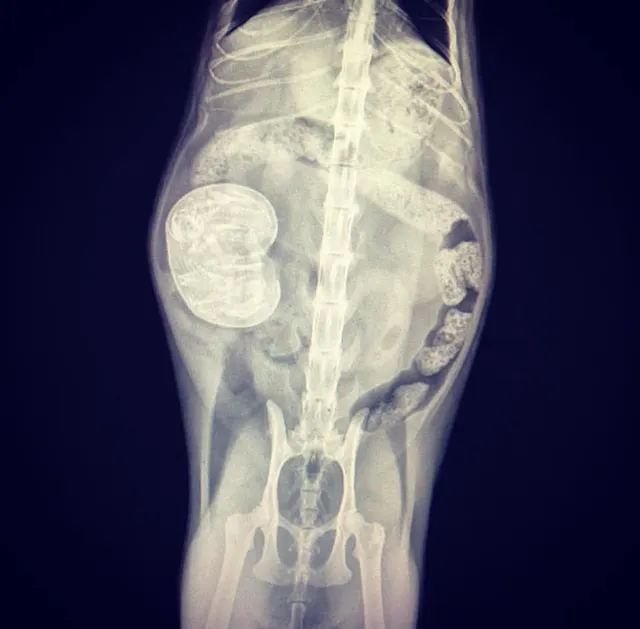

We asked our Facebook audience, "what is the coolest clinical photo you have on your phone right now?" The response was overwhelming. We sorted through more than 600 responses to find our favorite radiographs. Here are those images and their stories. Thank you to everyone who shared their photos.

"This energetic 10-month-old Labrador swallowed a 12-inch serrated knife. The puppy was bouncing off the walls when he was brought in and it was hard to keep him still. Surgery went well and amazingly, nothing was damaged!"—Katelyn E